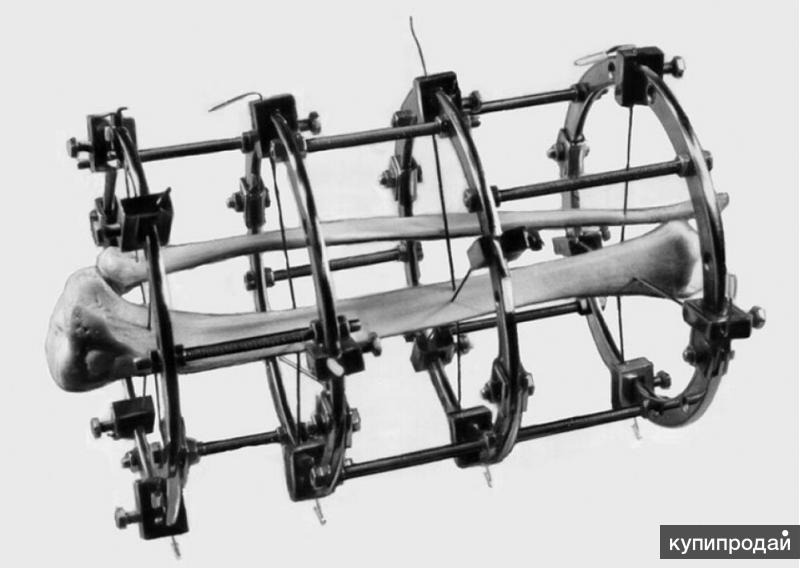

Аппарат Илизарова: принцип работы и применение

Раздел: Моменты озарения